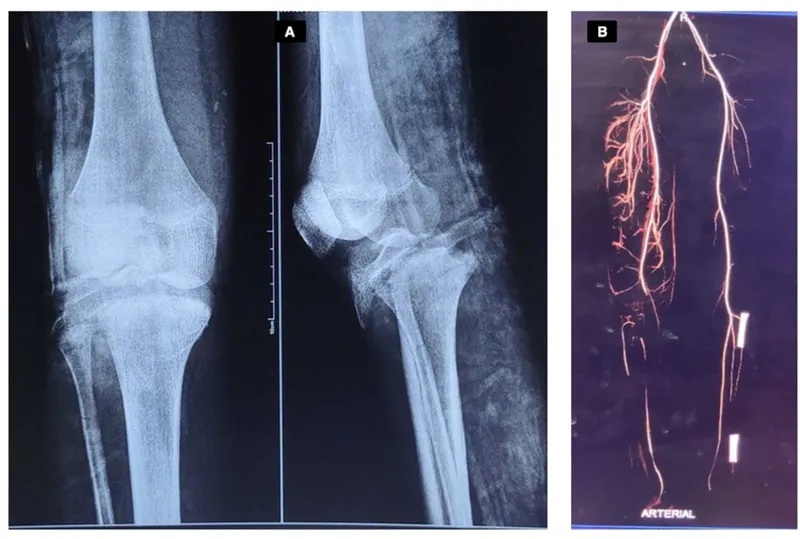

⭐ Following a knee dislocation, a normal distal pulse does NOT rule out a popliteal artery injury. Perform an Ankle-Brachial Index (ABI); if < 0.9, a CTA is mandatory due to high risk of intimal tear and delayed thrombosis.

- Knee dislocations carry a high risk of popliteal artery injury.